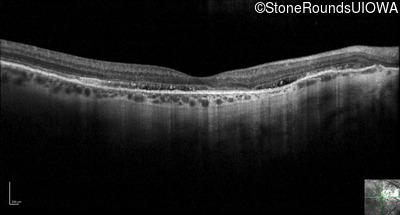

Optical Coherence Tomography - Left - 20/30 -2 sc

Exemplar / OCT Stack

OCT Stack